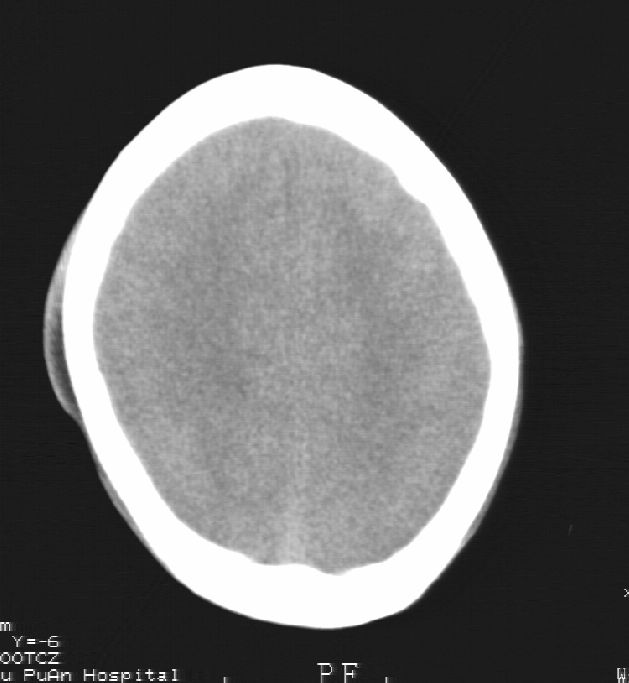

患者男,22岁,因外伤入院,低密度影ct值约-120hu。

脑水肿,头皮下血肿,胼胝体发育不全、合并脂肪瘤及钙化;建议必要时行mri检查。